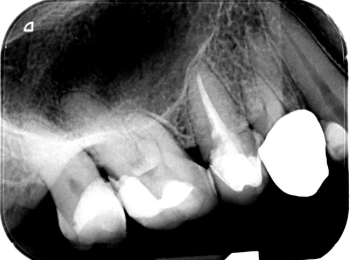

Röntgen Krone distal

25: apikal aufgehellt, Krone distal undicht, WF reicht nicht bis ins untere Drittel.

26 und 27 nicht erhaltungswürdig, vertikaler Knocheneinbruch.

Röntgen Revision 25

Zustand nach Revision 25 und Extraktion 26 und 27.

Röntgen Ausheilung

Zustand nach Ausheilung 25 apikal nach Revision und Regio 26 und 27 nach Extraktion.